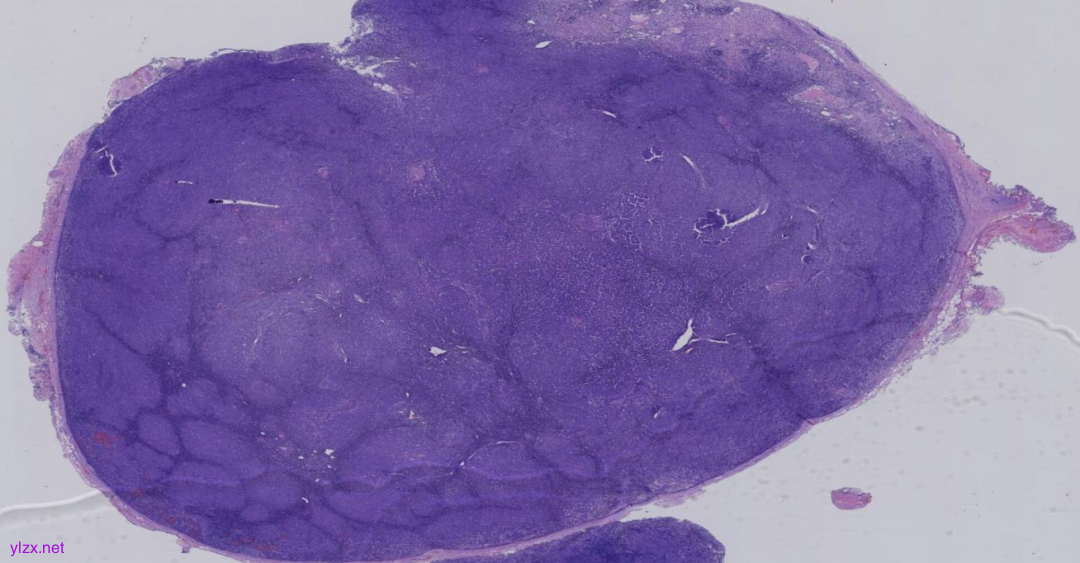

大体所见

淋巴结1枚,直径1.8cm,切面灰白质嫩。

图1:低倍镜下淋巴结内见大小不等的结节状结构,是一个以结节性生长方式为主的淋巴组织增生性病变,局部淋巴结被膜增厚。